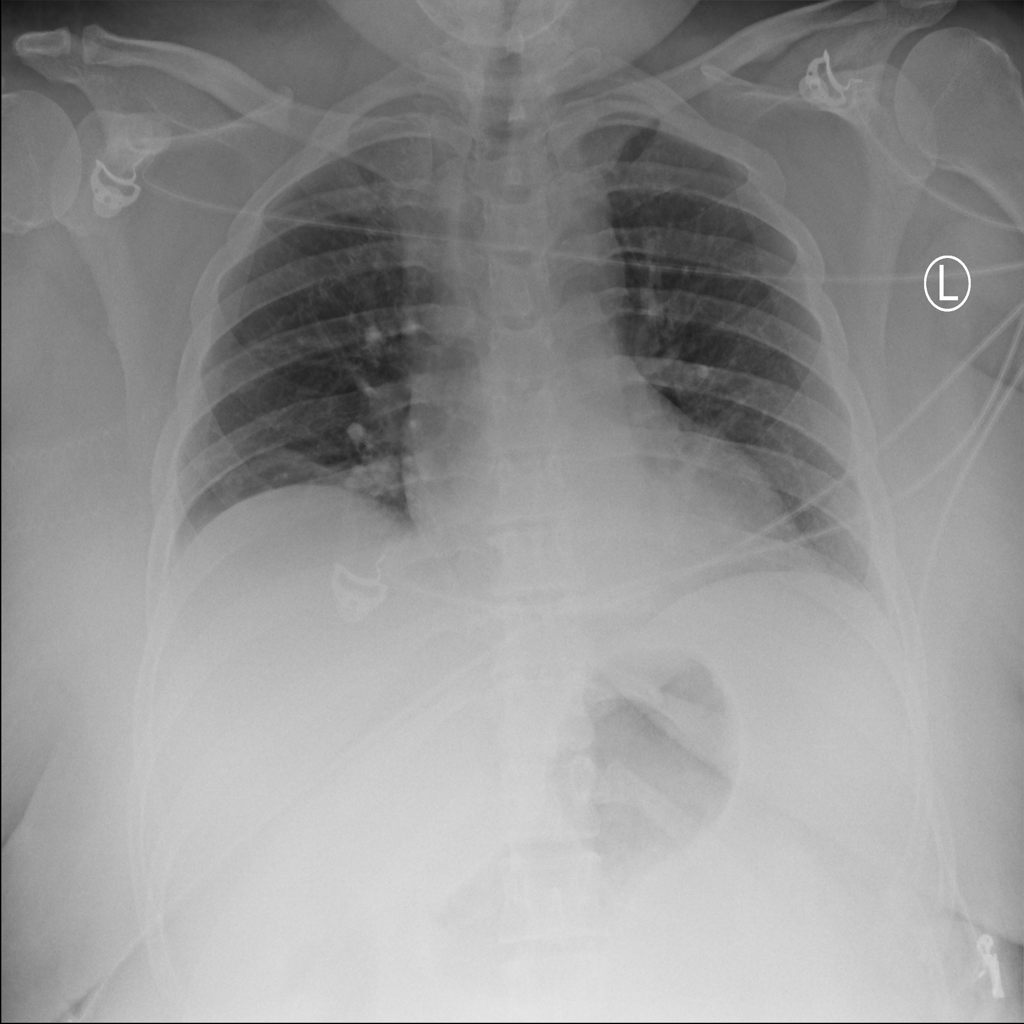

PAT-F3E7 · IMG-000Cardiomegaly

PAT-F3E7 · IMG-000

PA